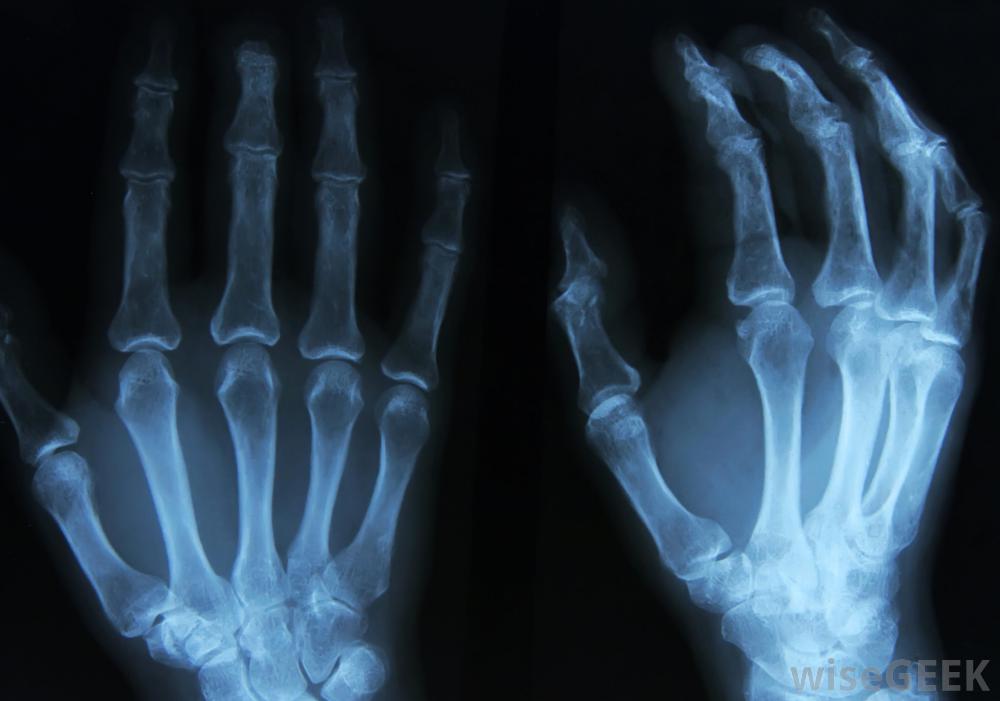

如果医生怀疑内生软骨瘤导致骨折,可以进行X光检查不清楚为什么会出现内生软骨瘤,但可能是胚胎软骨在已经发育好的骨骼内不断生长的结果。这种软骨瘤最常见于10至20岁的儿童和青少年,在男性和女性中出现的比率几乎相同。内生软骨瘤通常无痛,不会被发现,除非医生在对其他损伤或情况进行诊断测试时会注意到这一点。

如果医生怀疑内生软骨瘤导致骨折或畸形,他或她通常会采取x光片,磁共振成像(MRI)扫描,或其他影像学检查来确认诊断。当MRI或x光结果显示内生软骨瘤时,医生会根据大小、位置决定最佳治疗措施,对医生来说,仔细检查骨肿瘤以确保它们没有癌变的迹象是很重要的。手术固定骨折或变形的骨头通常足以防止将来小范围的不良反应内生软骨瘤。大的肿瘤通常在精细的外科手术中被切除,包括用手术刀刮去内生软骨瘤,并将新的组织移植到骨上。病人通常需要在手术后回到医生的办公室进行常规的核磁共振扫描,以监测骨愈合情况肿瘤复发,虽然一个内生软骨瘤的人可能在身体的不同部位有其他未被发现的肿瘤

当X光检查结果显示内生软骨瘤时,医生将根据肿瘤的大小和位置决定最佳治疗方法。